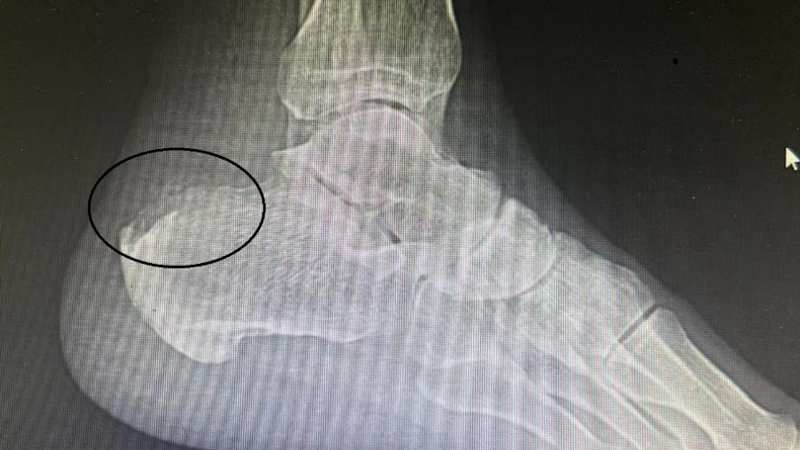

术前可见跟骨后上结节异常骨性凸起(Haglund畸形)

术后复查畸形消失